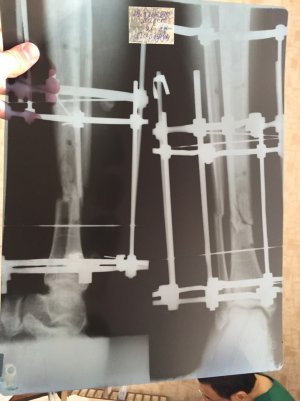

Здравствуйте доктор мне 26 лет , 29 июля 2016 года я получил травму на соревнования открытый перлом голени бб и мб кости , 12 августа поставили аппарат илизарова , 12 ноября сдела снимок костная мозоль слабая нормально ли это? с 16 ноября начал наступать на ногу даю вес 30кг , до этого не наступал

добавил снимки сделанные 29сентября и 12 ноября